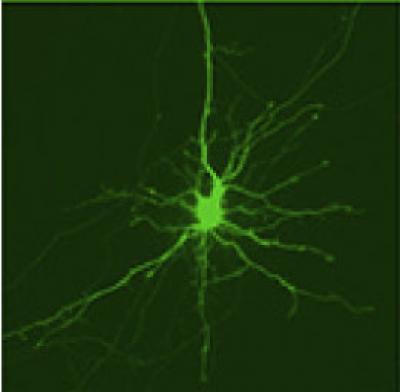

To measure how quickly proteins are cleared away from cells, the researchers developed a new technique called optical pulse-labeling, allowing them to follow specific proteins in individual living cells. To test the technique, they grew brain cells in a dish and turned on Dendra2, a photoswitchable protein that glows from green to red after being hit by a specific type of light. Both the red and green glow can be followed until the protein is cleared from the cell. In this way, the researchers could track the lifetime of newly produced Dendra2 (which glows green) and older, photoswitched Dendra2 (which glows red) until the protein was cleared away from the cell.

The researchers followed Dendra2 in a set of striatal neurons, which they obtained from rats. The striatum (where striatal neurons are located) is a brain region involved in a number of brain functions including planning movements and is most heavily affected in Huntington's disease. They discovered that the mean lifetime of the protein (how long it remained in the cell) varied three- to fourfold, suggesting that rates of proteostasis were different among individual neurons. In other words, some cells may process an identical protein much slower than others.